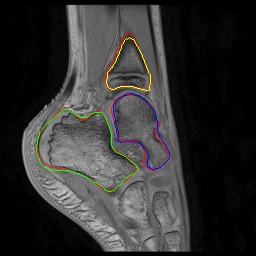

Fig. 2: Visual comparison of UNet regularization methods: baseline UNet [2], adversarial regularization [6], shape priors based regularization [7] and the proposed shape priors based adversarial regularization on ankle dataset. Ground truth delineations are in red (). Predicted bones, calcaneus, talus and tibia respectively appear in green (), blue () and yellow ().

Experiments were conducted on two pediatric datasets previously acquired using a 3T Philips scanner [4]. The two MR images datasets were independently acquired on two musculoskeletal joints (ankle, shoulder) from a cohort of 17 and 15 pediatric patients. An expert (12 years of experience) annotated images to get ground truth contours of calcaneus, talus and tibia for ankle, as well as scapula and humerus for shoulder. All axial slices were downsampled to 256×\times256 pixels.

We compared the proposed shape priors based adversarial regularization method (SPAR in Fig.1) with baseline UNet (Base. UNet) [2], adversarial regularization (Adv. Reg.) [6] and shape priors based regularization (Sh. Reg.) [7]. For all methods, the backbone UNet architecture and all training hyper-parameters remained the same. All networks were trained from scratch with randomly initialized weights.

From the quantitative results (Tab.1), our method achieved competitive results compared to state-of-the-art on both datasets. On ankle dataset, our approach ranked best in Dice (92.7%percent\%), RAVD (8.0%percent\%), ASSD (0.8mm) and MSSD (8.1mm) metrics. For shoulder dataset, our method outperformed other approaches in RAVD (13.6%percent\%) while remaining second best in Dice (0.3%percent\% lower than the best) and ASSD (0.3mm higher than the best). We suspected that the high variability observed in shoulder results was due to the poor quality of two outlier examinations. The visual comparisons (Fig.2) provided the evidence of gradual improvements in segmentation quality of the regularized methods over baseline UNet. We wanted to report statistical significance tests to compare the performance of the employed methods but the required sample size determined using a power analysis (with typical statistical power β=0.8𝛽0.8\beta=0.8) was larger than our available datasets.